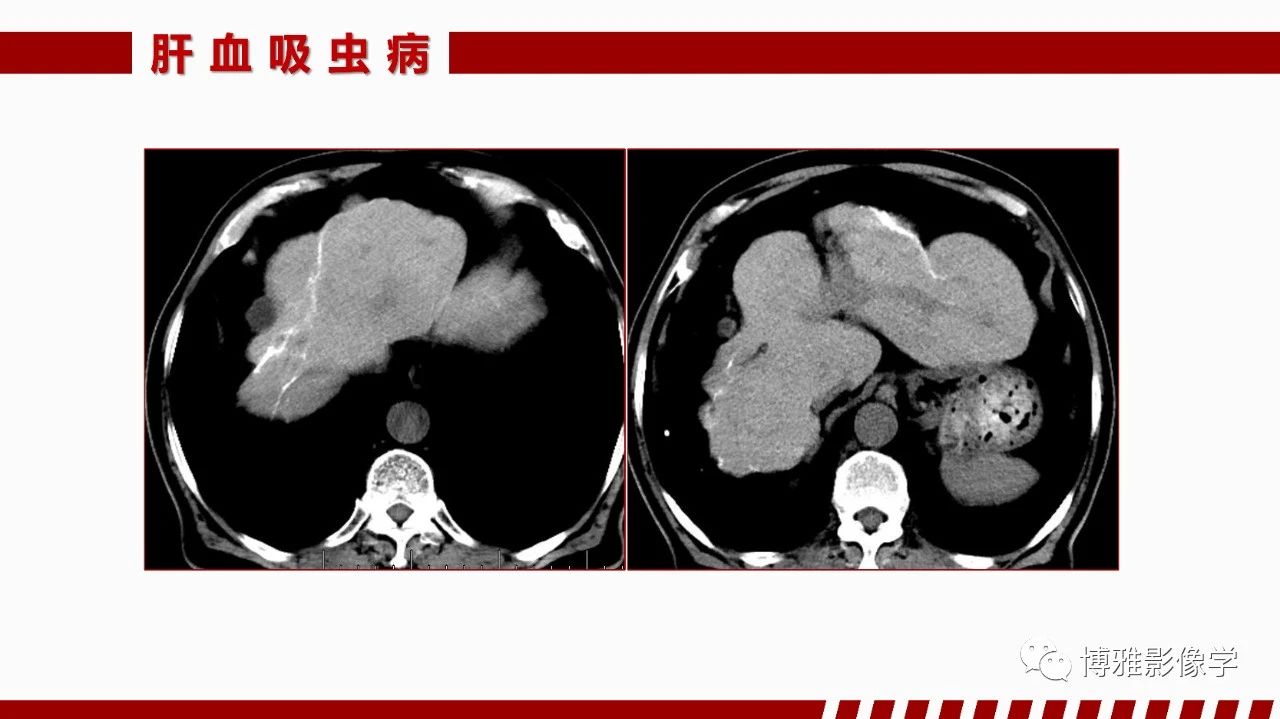

[腹盆] 肝脏感染性疾病的多模态影像诊断及鉴别

肝脏感染性疾病的多模态影像诊断及鉴别